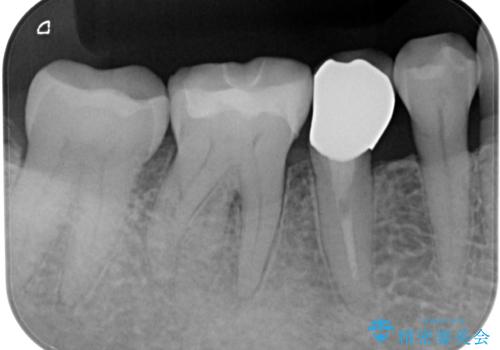

拡大鏡視野下で、ゴールドインレー、虫歯の除去を行い、セラミックインレーに適した形に整えました。

歯と歯茎の間に圧排糸と言われる糸を入れてシリコーン印象材にて型どりをしました。

特に異常もなく見た目、噛み合わせともに満足していただけました。

ラバーダム防湿を行い、セラミックの接着をすることで、唾液や血液などの接着阻害因子を排除することができます。